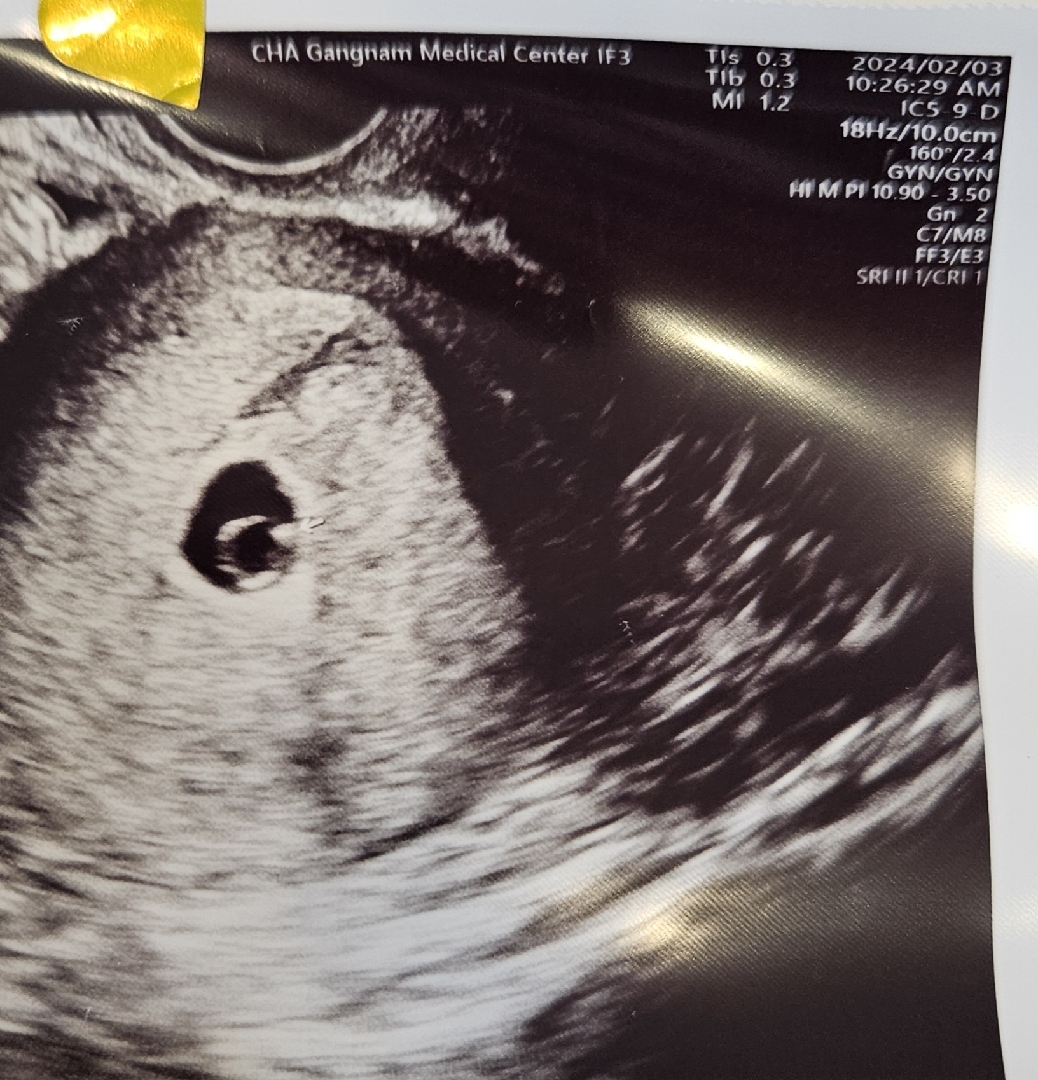

6주, 더딘 성장속도(5주크기)

안녕하세요 저는 막생리는 23.12.12구요 24.01.01 배란유도(?)주사 맞고 숙제 1.2숙제 1.3숙제 1.6숙제 하고 현재 6주정도 됩니다. 1.29 이번주 월요일에 아기집이 크기도 좋고 자리 잘 잡았다는 촘파도 보구요 임신확인서도 받았어요 예정일 24.09.25 (난황은 안보였구요) 오늘 주병원에서 촘파먼저하고 진료보는데 촘파검사시 아기집+난황+콩만한 👶아가 도 보여서 기분이 좋았어요 근데 진료보는데 다소 심각한 표정의 원장님께서 상황이 좋은 건 아닌것 같다고 하시면서 6주정도 되는데 아기는 5주크기라고 한주정도 차이가있고 성장속도가 느린것 같다고 하셨습니다. 성장이 느린걸수도있고 착상이 늦어진걸수도 있어서 알수는 없지만 유산도 될수도있고 성장이 느렸다 자랄수도 있다고하셨는데 괜시리 마음이 울적하네요 혹시 저와 같은 분이 계시는지 긍정적으로 생각해야지 하는데, 심란한맘에 적어봅니다🥹 * 그리고 제가 본의아니게 주병원,서브병원 이렇게 다니게됐는데 오늘 촘파보고 다음주 월요일에도 촘파 예약이 있는데 혹시 자주 촘파 보는게 안좋은 영향을 미치기도 하는지 궁금합니다. 읽어주셔서 감사합니다.

뇽끼님 따수운 말씀 감사합니다🥹🩷안그래도 오늘 다녀오는데 첨으로 심장뛰는걸 봤어요(그래서 더울컥🥹😂아직 쪼꾸매서 뛰는것만 봤고 잘 안들린대요) 한 주 정도 차이나는건 큰 문제는 아니라고 하셨는데 다음주의 성장여부에 따라 이제 갈리나봐요. 할 수있는건 없으니 걱정말구 기다려볼게요😌 감사합니다.

제가 막생 12월 21일이었는데 2월 3일날 6주 1일로 보인다고 하시고 아기 크기는 0.5센치였어요! 호프리님은 막생 기준이면 5주차일거같은데 좀더 기다려보셔도 되지 않으실까요? 넘 걱정마셔요!